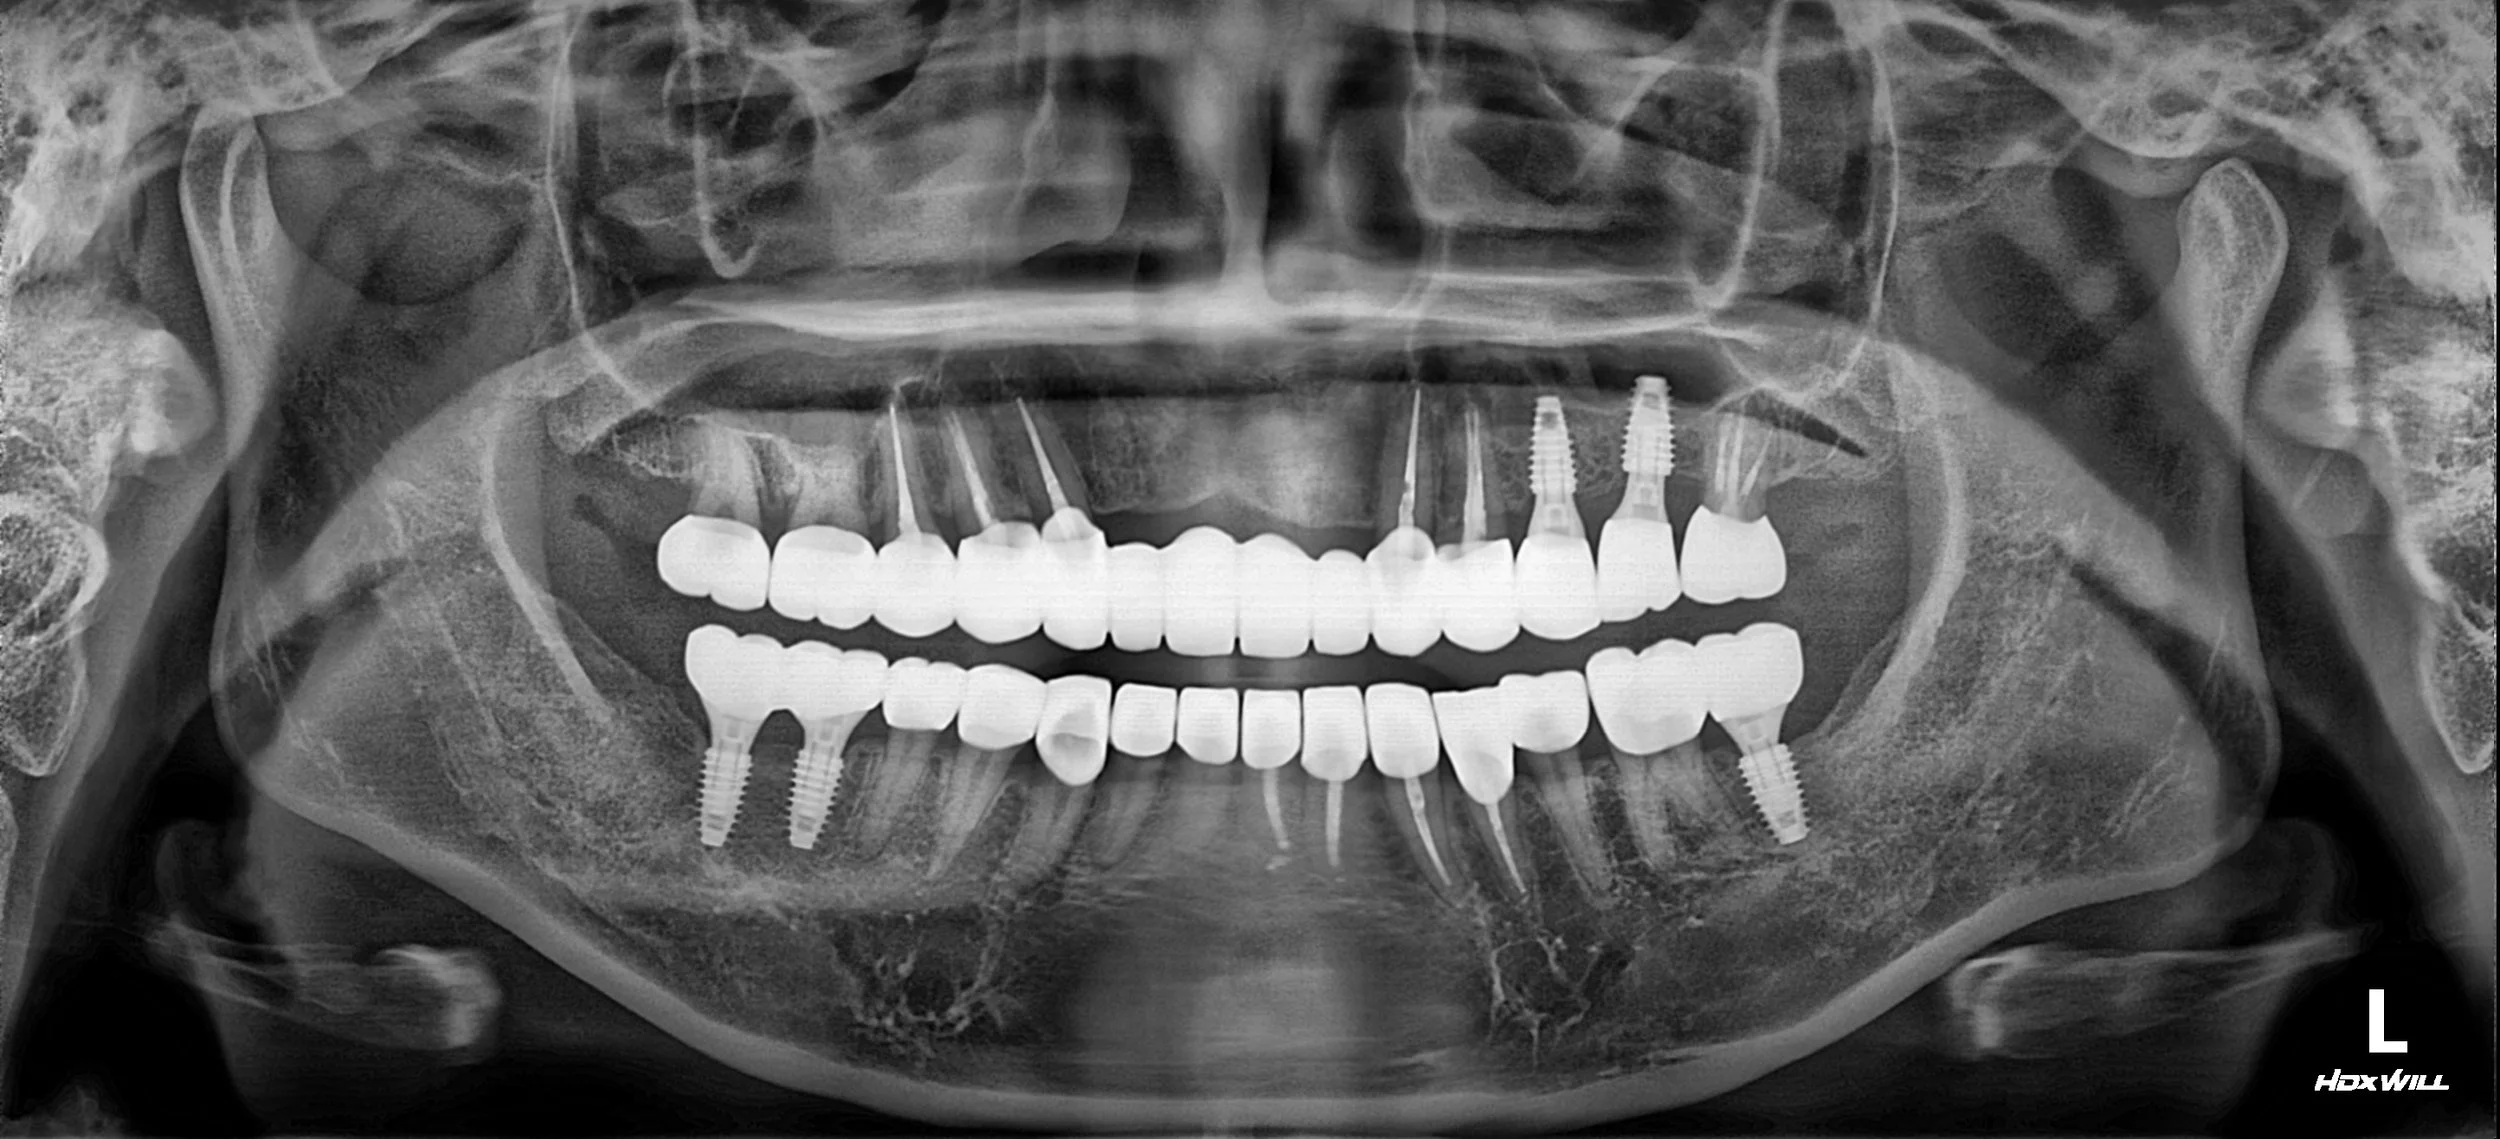

3. VDO Management & Implant Surgery: The vertical dimension of occlusion (VDO) was reset to a more physiologically neutral height. Temporaries were used to stabilize the bite. Following GBR, strategically placed implants were integrated into the posterior edentulous regions to serve as the primary occlusal stops.

4. Prosthetic Integration: Precision-milled fixed bridges were fabricated. A combination of tooth-supported and implant-supported restorations was used to achieve a harmonious and balanced occlusal scheme.